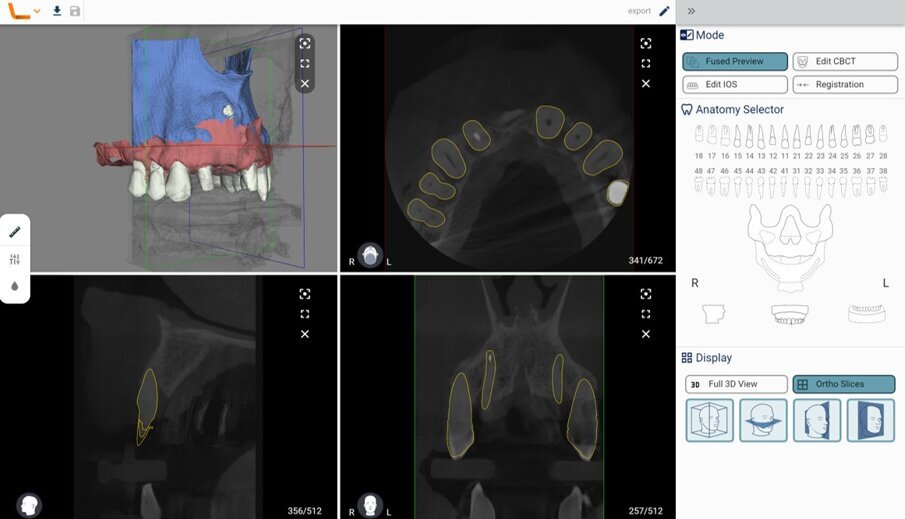

I dati Digital Imaging and Communication in Medicine (DICOM) derivanti dalla CBCT, insieme con il file standard tesselletion language (.STL) ottenuto tramite la scansione intraorale, venivano quindi caricati in cloud in un software di Intelligenza Artificiale (Virtual Patient Creator, RELU). Tali dati venivano elaborati e il software di Intelligenza Artificiale restituiva, in meno di 10 minuti, la ricostruzione 3D della maxilla del paziente, ottenuta tramite segmentazione ossea automatica, accoppiata e allineata alla scansione intraorale (Fig. 4). Il software, inoltre, restituiva la segmentazione di ciascun singolo elemento dentario, sotto forma di files .STL separati, nei quali la corona veniva direttamente dalla scansione intraorale, mentre la radice dalla CBCT (Fig. 5). La “fusione” automatica del dato della CBCT con quello della scansione intraorale, e il perfetto allineamento tra le strutture anatomiche, rappresentava il risultato dell’applicazione dell’Intelligenza Artificiale. La stessa area rigenerata veniva opportunamente segmentata (Fig. 6). A questo punto, l’operatore era in grado di visualizzare tutte le strutture, selezionare quelle interessanti ed esportarle come files .STL. Tali files venivano quindi caricati all’interno di una applicazione dedicata per l’uso per la realtà aumentata (Holodentist, Fifthingenium), insieme con la libreria implantare del sistema scelto (Naturactis, Lyra ETK) per la risoluzione dello specifico caso clinico (Fig. 7). L’operatore vestiva quindi gli occhialini per la Realtà Aumentata (MagicLeap2, Magic Leap) e, anche attraverso l’aiuto di uno specifico joypad, era in grado di pianificare l’impianto in 3D nell’esatta posizione, profondità ed inclinazione, impiegando gli ologrammi (Clicca QUI). Terminata la pianificazione e salvata la posizione dell’impianto, essa veniva esportata e impiegata per disegnare, all’interno di software open-source, un template per una chirurgia guidata statica (Figg. 8, 9). Dal momento che Intelligenza Artificiale e Realtà Aumentata non possiedono ancora le certificazioni per l’impiego clinico, tutti i files erano quindi re-importati all’interno di software radiologico certificato (MIMICS, Materialise) per il controllo della posizione implantare nelle cross-sections radiologiche (Figg. 10, 11).

Fig. 4_Intelligenza Artificiale (Virtual Patient Creator, RELU): segmentazione CBCT e allineamento automatico CBCT-IOS.